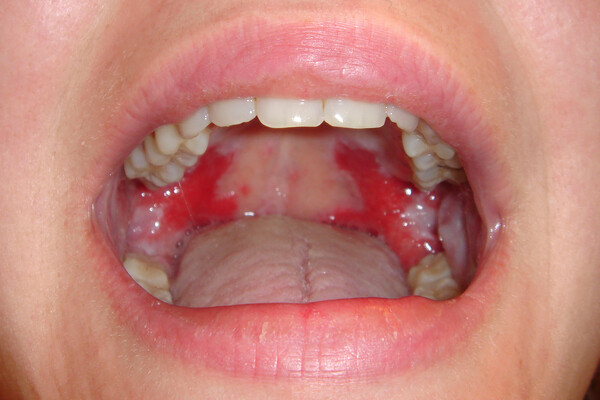

What Causes Red Spots On The Roof Of Your Mouth?

Red spots on the roof of your mouth can be caused by a variety of different reasons. Some are just a minor inconvenience, while others could be a sign of a more serious health issue that may require further investigation. Here are some common possibilities:

Canker Sores

Most people have had a canker sore at some point in their lives, and while these sores are more common on the inside of the cheeks or lips, they can occur anywhere including the roof of the mouth. Canker sores are generally a result of stress, eating particular foods, or coming in contact with other irritants. The sores normally start as small, red bumps and often develop a white center. There are over-the-counter treatments available, and most sores will heal in a week to 10 days.

Candidiasis

Also known as thrush or oral candidiasis, this fungal overgrowth can cause red bumps and white patches inside the mouth. Common in those with dentures and diabetes, candidiasis is most often treated by preventing the overgrowth in the first place. According to the ADA, oral antifungals may also be used to combat particularly tough cases. Learn more about thrush in the Colgate Oral Care resources.